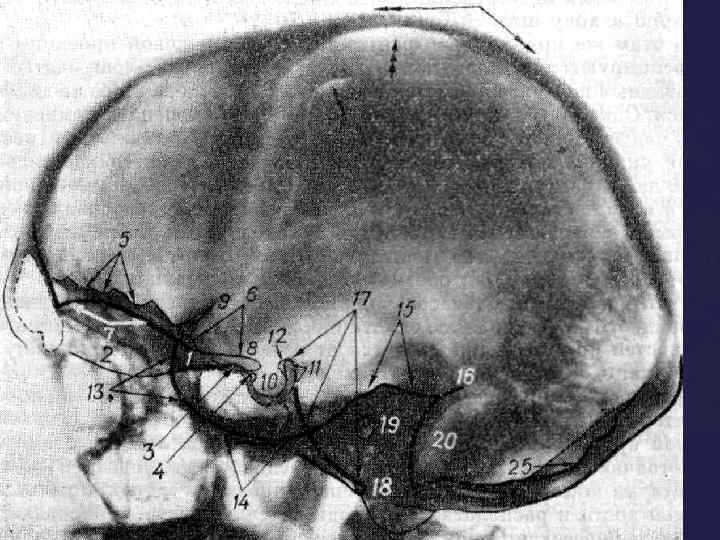

При изучении рентгенограмм черепа необходимо учитывать следующие моменты: 1)Наиболее интенсивную тень дают плотные участки костей (каменистая часть височной кости, скуловая кость). 2) Глазница и воздухоносные полости выглядят как просветления. В боковой проекции хорошо видно турецкое седло. По его размерам и степени сохранности судят о величине гипофиза. Изучение R-гр. черепа

При изучении рентгенограмм черепа необходимо учитывать следующие моменты: 1)Наиболее интенсивную тень дают плотные участки костей (каменистая часть височной кости, скуловая кость). 2) Глазница и воздухоносные полости выглядят как просветления. В боковой проекции хорошо видно турецкое седло. По его размерам и степени сохранности судят о величине гипофиза. Изучение R-гр. черепа